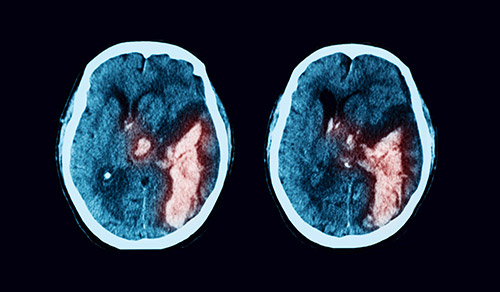

Innovative technologies and alternatives to traditional treatments are transforming the diagnosis and management of neurological conditions. In 2025, NewYork-Presbyterian physicians and surgeons from Columbia and Weill Cornell Medicine used sonication and convection-enhanced delivery to penetrate the blood-brain barrier, validated an adjunctive treatment for subdural hematoma, broadened access to spine surgery, advanced experimental therapies for neurodegenerative diseases, and more. Our specialists have been steadfast in reshaping the fields of neurology and neurosurgery in the pursuit of better patient outcomes and enhanced quality of care.

From cutting-edge research to compassionate patient practice, neurologists and neurosurgeons from Columbia and Weill Cornell Medicine are at the forefront of developing and applying the most advanced approaches to treat debilitating conditions affecting the brain and spine. With a broad range of focus on neurodegenerative and neurovascular disorders to malignant tumors, our innovative and advanced care is leading to new treatment options and enabling patients to achieve the best possible outcomes.